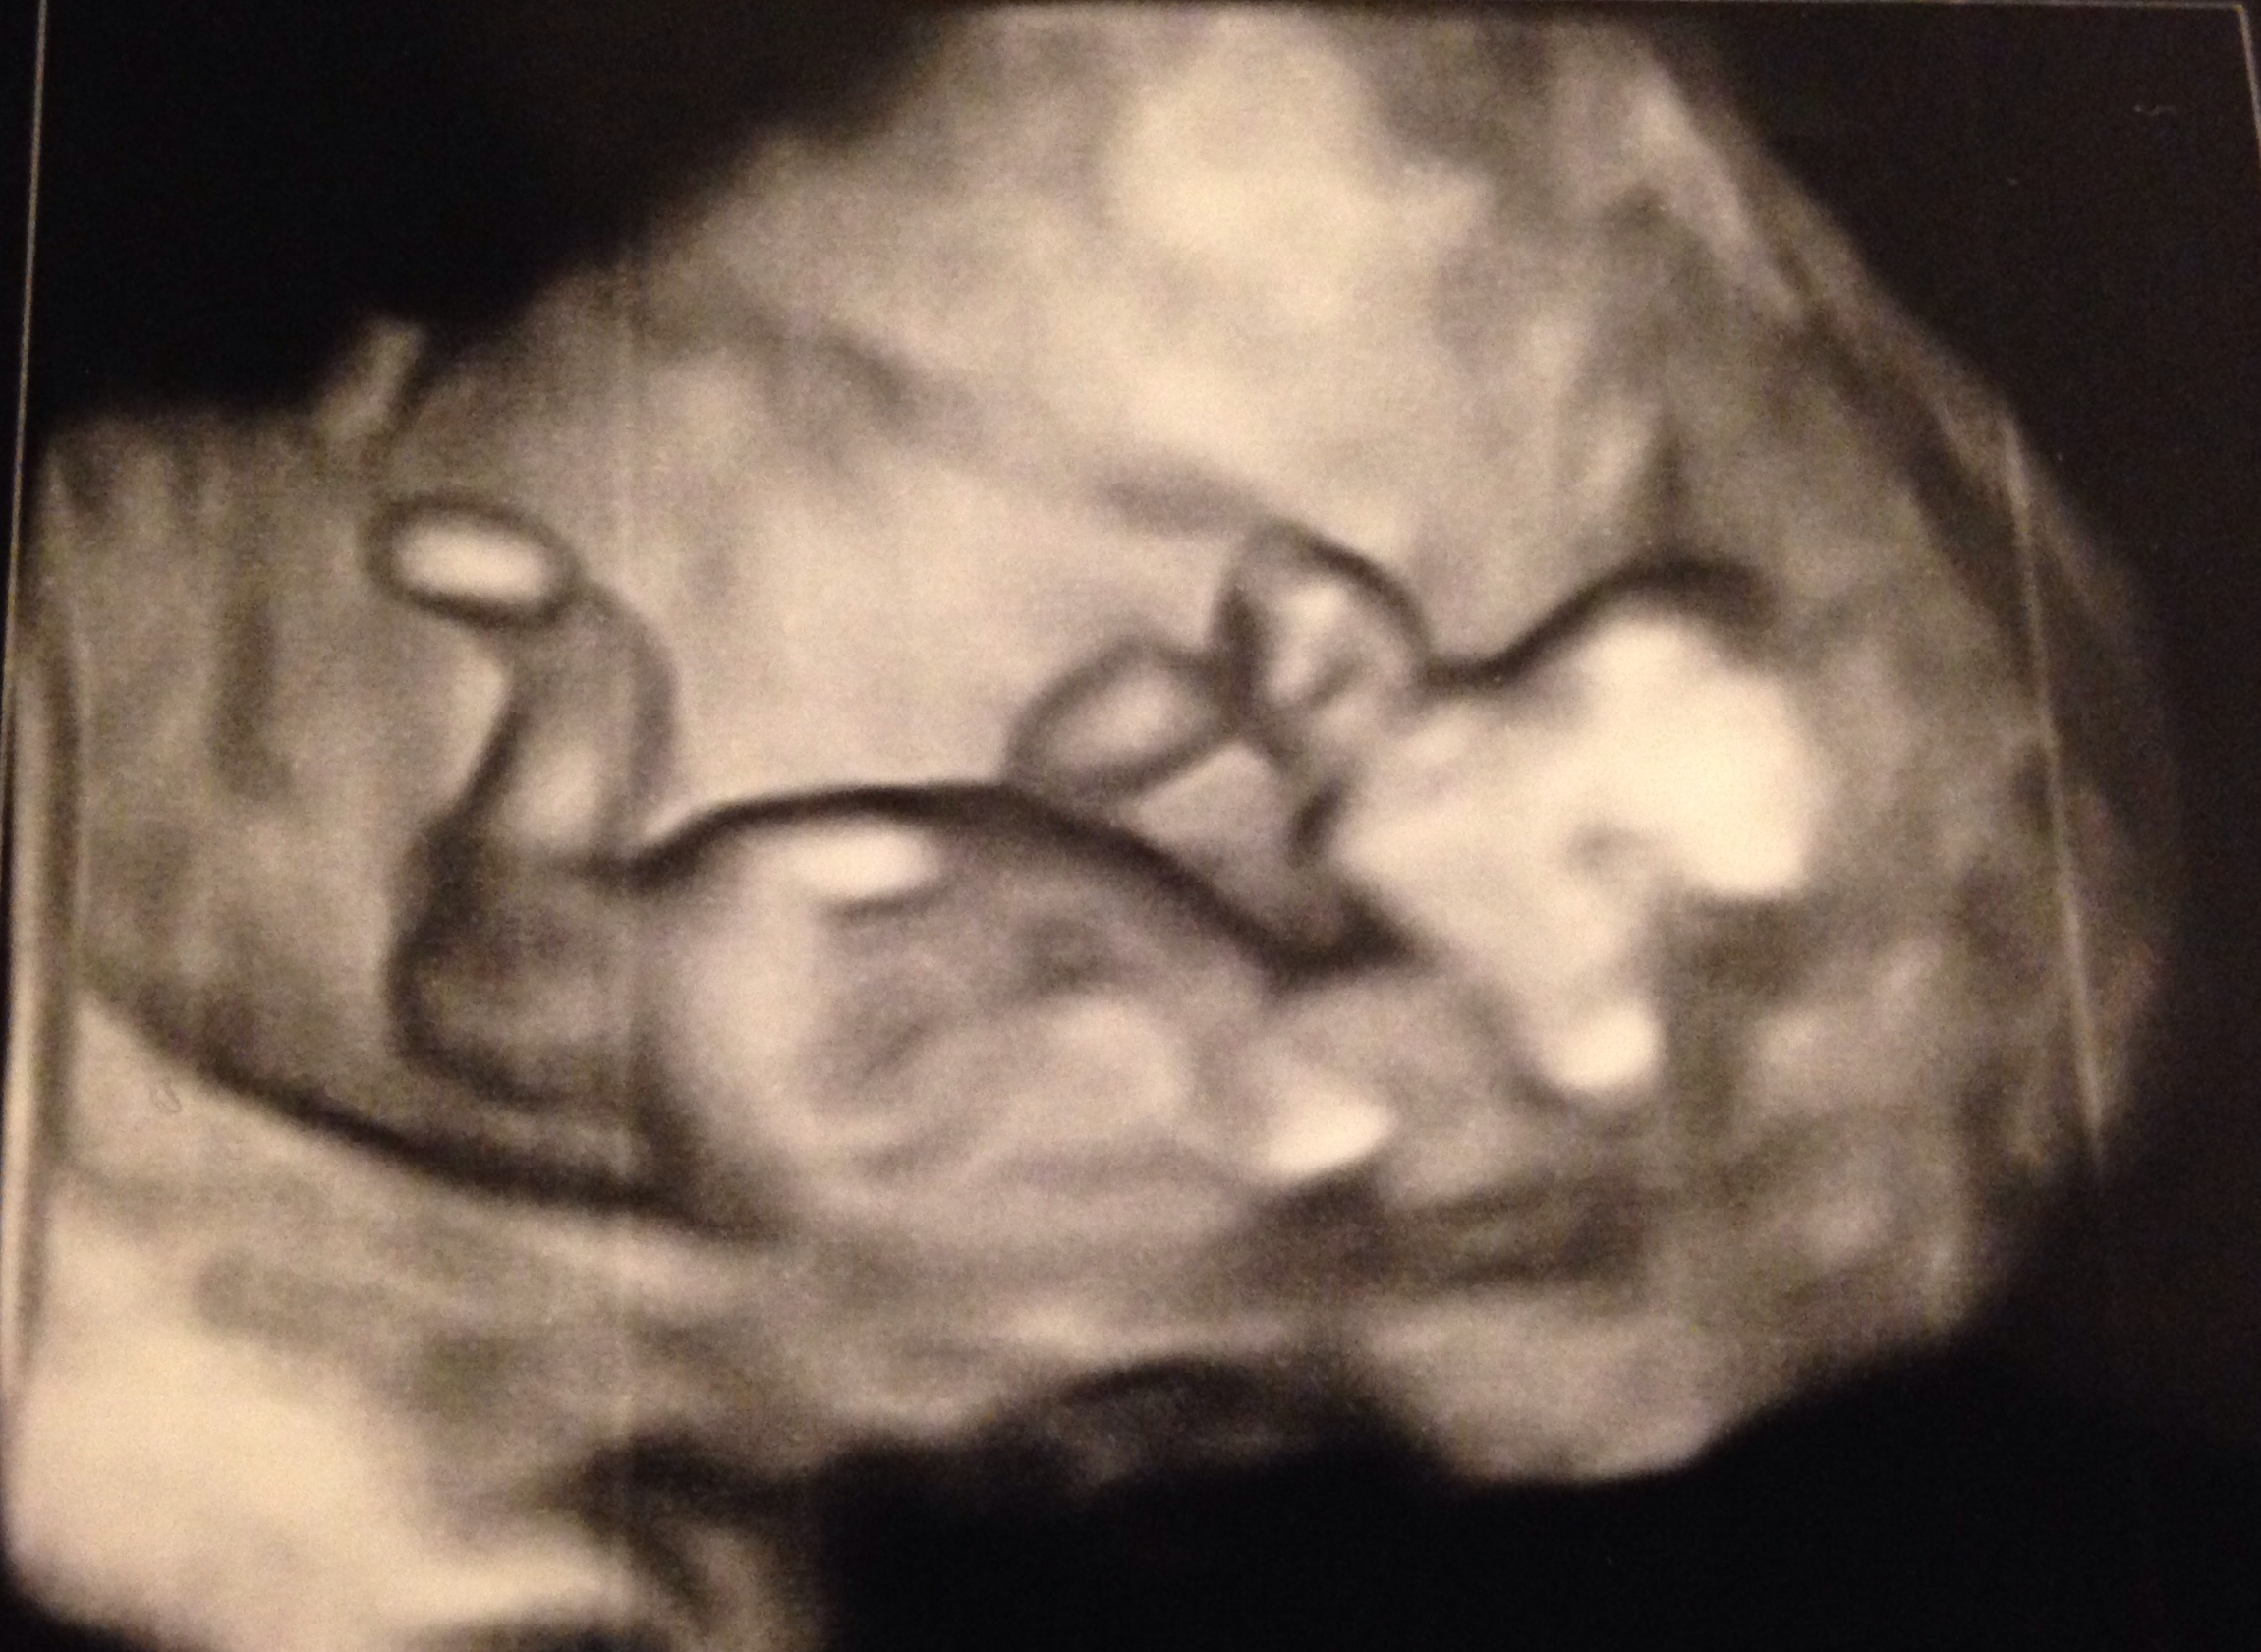

This was at 12 weeks. Now at 13+2. I'm in love with the little fingers and toes already